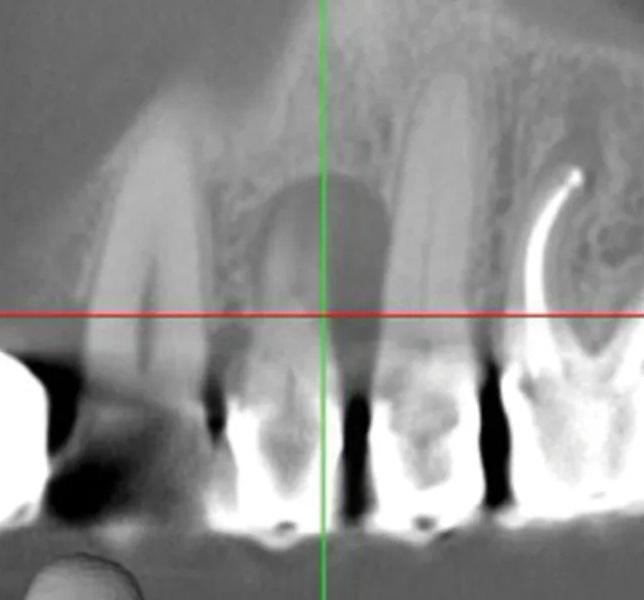

Пациент мужского пола 68 лет был направлен эндодонтистом с диагнозом симптоматический необратимый пульпит с нормальными периапикальными тканями и значительной потерей костной ткани с вовлечением фуркации у первого премоляра верхней челюсти слева (зуб № 2.4). Из-за состояния пародонта была показана реабилитация с помощью имплантационной реставрации. Конусно-лучевая компьютерная томография (КЛКТ) выявила потерю кости с дистальной стороны пораженного зуба, размером 5 мм в ширину и 9 мм в длину соответственно, с вовлечением альвеолярного костного гребня (Фото 1 – Фото 4).

Фото 3. Предоперационный корональный срез КЛКТ первого премоляра верхней челюсти слева.

Фото 4. Предоперационный сагиттальный срез КЛКТ первого премоляра верхней челюсти слева, демонстрирующий область рентгенопрозрачности, вовлекающую более двух третей корня, включая пришеечную область и альвеолярный костный гребень.